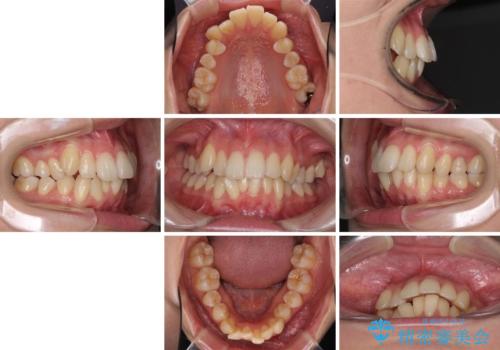

- 上の前歯、および下の歯列全体のでこぼこを気にして来院された患者様です。

インビザラインを用い、IPR(歯と歯の間を削る)と歯列全体を後方に移動させることで、歯並びを整えていくこととしました。

歯列全体を後方に移動させるため、下顎の親知らず2本を抜歯することとしました。